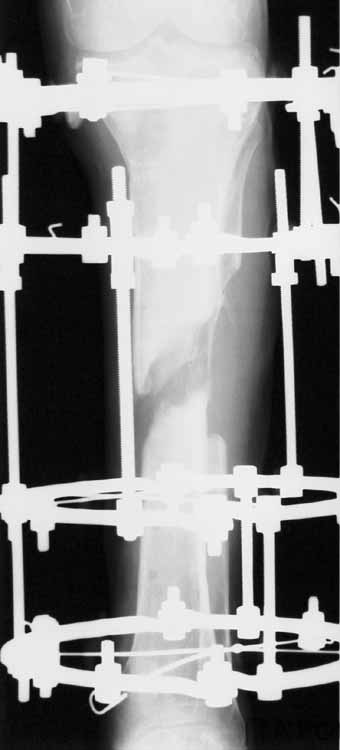

С места аварии в районную больницу, где произвели ампутацию правой голени. Дальше в клинику спец. помощи, где на левой голени были удалены нежизнеспосбные инфицированные отломки, (дефект 13 см) и наложен аппарат Гофмана. Детали неизвестны. Со слов больного, инфекционный процесс левой голени купирован не был. В феврале аппарат был снят и произведен остеосинтез гвоздем (before1;2). В мае, объективно: В нижней трети голени функционирует свищ, отделяемое гнойное: золотистый стафилокок, чувствительный к большинству антибиотиков.

1 июня произведено удаление гвоздя, дренаж костномозгового канала, остеосинтез аппаратом Илизарова ( after 1; 2).